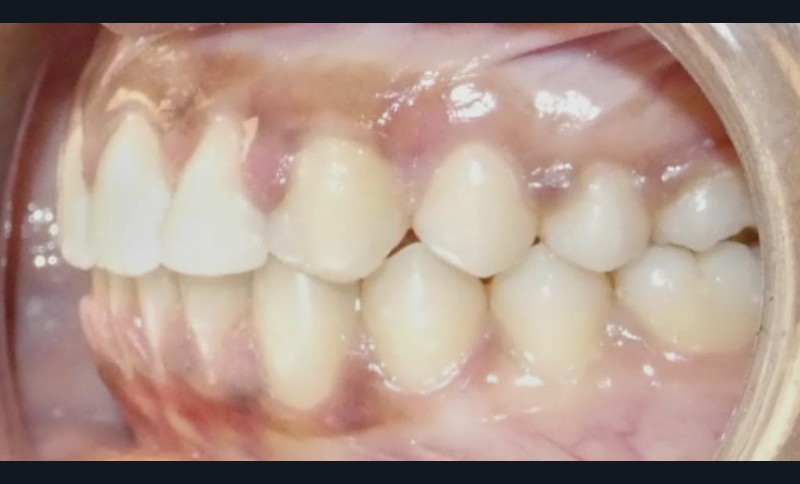

Diagnostic (fig. 1 et 2)

À l’examen extra-oral, la patiente présente un profil biprognathe associé à une Classe II squelettique modérée dans un contexte de normodivergence. L’angle naso-labial apparaît ouvert, le sillon labio-mentonnier est marqué et une prochéilie mandibulaire est observée. Le sourire se révèle disharmonieux, avec une faible visibilité des dents maxillaires.

À l’examen intra-oral, les arcades sont paraboliques, la courbe de Spee est normale. On remarque l’absence de la 23 sur l’arcade ainsi que la persistance de la 63. La patiente présente une Classe II partielle molaire et canine subdivision droite, ainsi qu’une insuffisance de recouvrement. Un léger encombrement incisif mandibulaire est présent, ainsi que des diastèmes maxillaires avec une dysmorphie dento-dentaire de 12 et 22.

L’examen fonctionnel révèle une ventilation nasale et une déglutition mature.